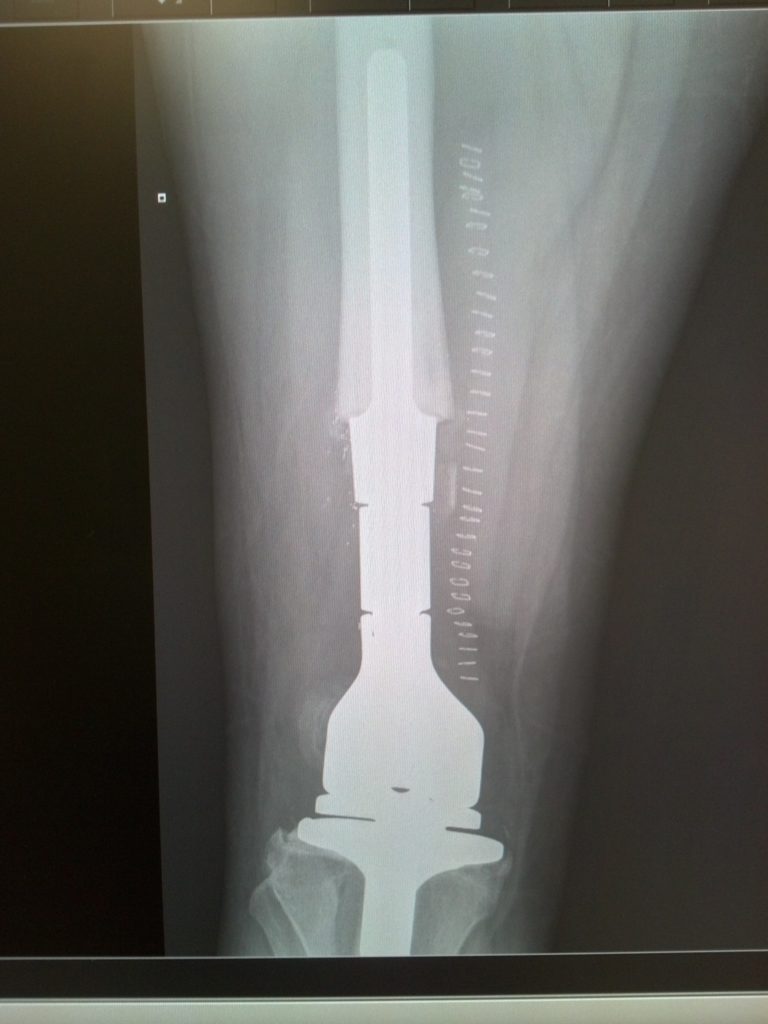

After his diagnosis, Anderson’s football career officially ended. Doctors performed surgery to remove the tumor, replacing his ACL, MCL and PCL with a metal rod. Shortly after hearing the news, Coach Nemec called Ohio State’s then-football coach, Jim Tressel, who sent a box of handwritten letters to Anderson from each and every player and coach apart of the Buckeye’s football program.